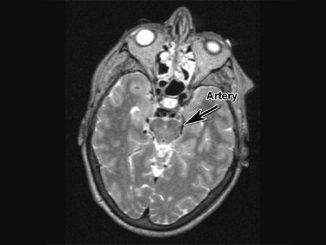

Arterial stiffness may be a novel risk factor for childhood and adolescent metabolic disease

Arterial stiffness may be a novel risk factor for metabolic syndrome in teens, a paper published in the American Journal […]